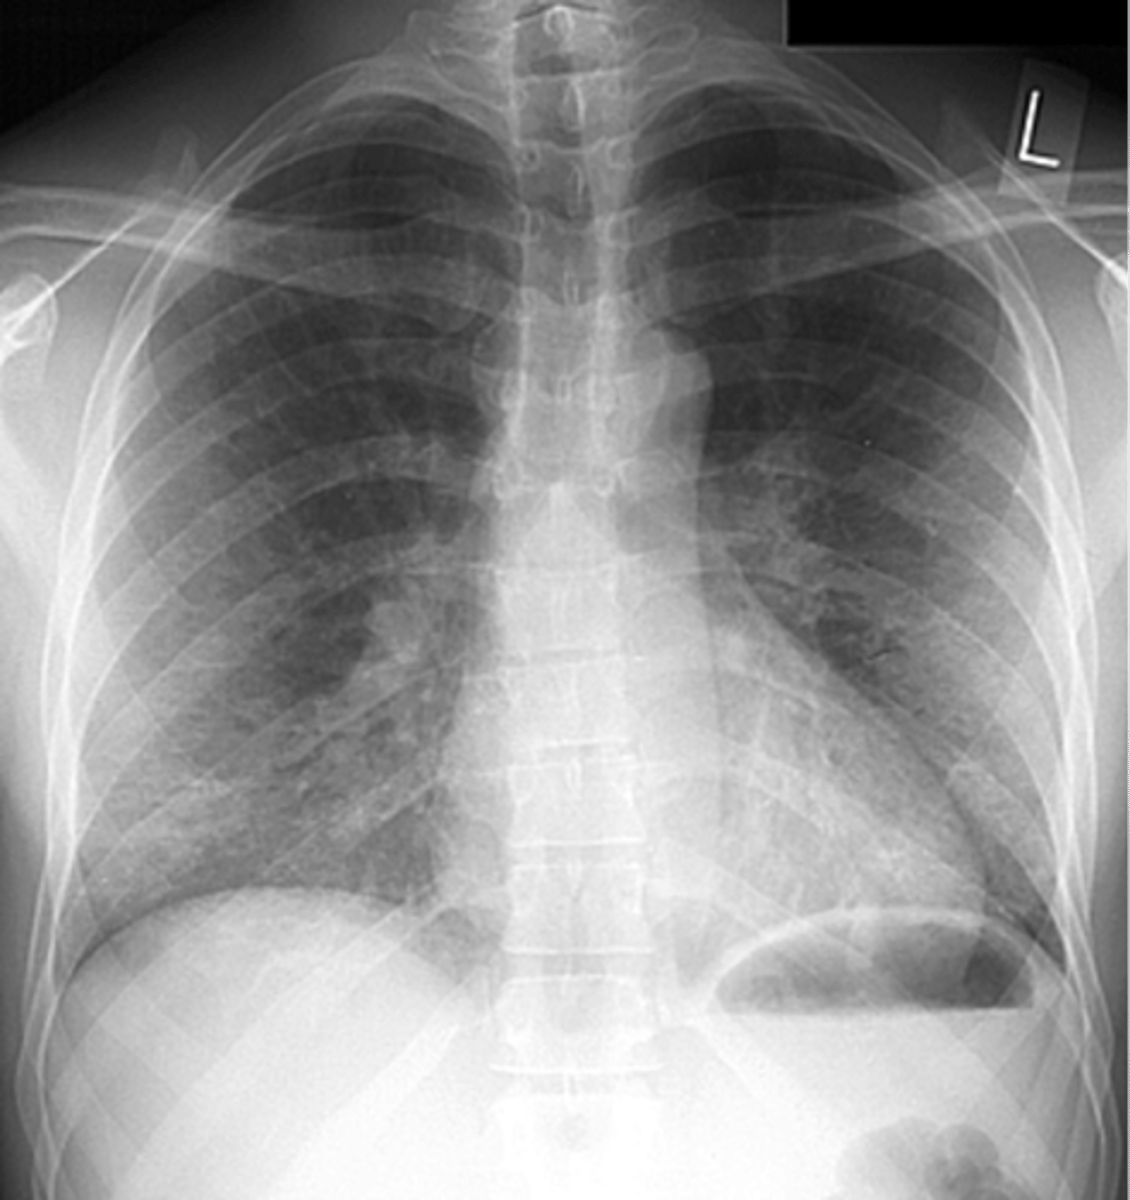

Bilateral interstitial infiltrates

air bronchogram- alveolar consolidation LUL